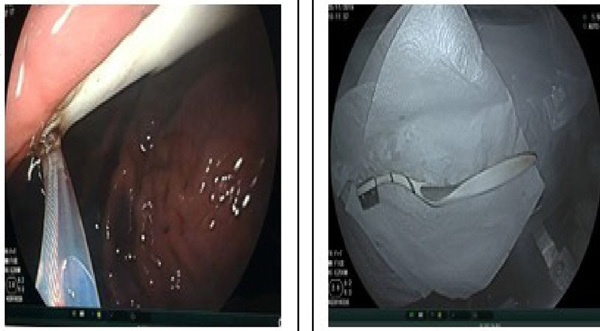

| Endoscopic image from the Hanoi Medical University Hospital. — Photo suckhoedoisong.vn |

Hanoi Medical University Hospital, who received the emergency case, said the endoscopic removal was successful in taking out the toothbrush.